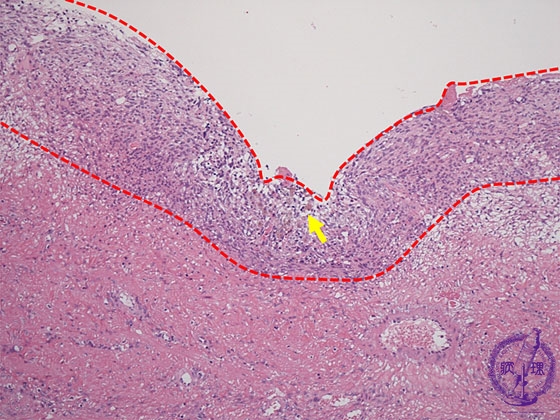

- 15.Female genital organs

- ★(2)Endometriosis

Histology (HE stain, low power): Ectopic endometrial tissue (stromal tissue), hemorrhage and hemosiderin-laden macrophages are apparent in the cyst wall (endometrial tissue: red dotted line, macrophages: yellow dotted line).

Click the image to see the enlarged image.